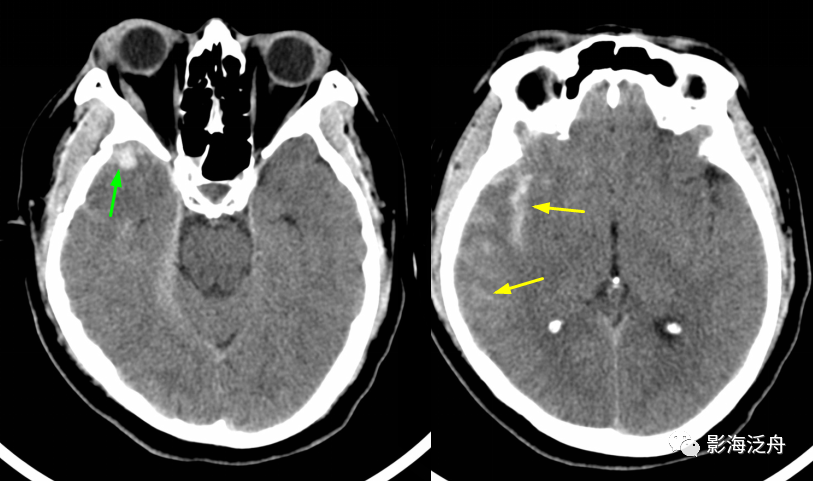

常见的急性颅脑损伤的ct和mri表现

来院时,患者神志模糊,急查头胸ct提示蛛网膜下腔出血,左侧颞枕部,右额